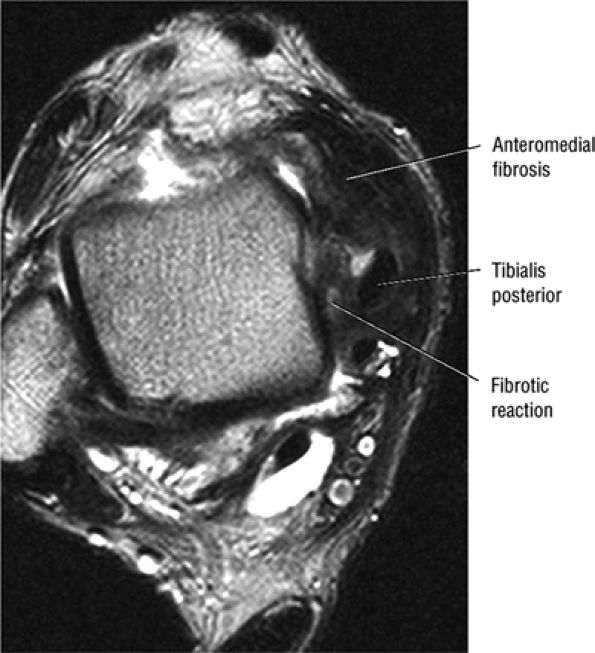

Medial osteochondral talar dome lesion. There is a fragment of osseous tissue within the osteochondral bed that may be attached by synovium. The fragment measures 8 mm anterior to posterior and 3 mm medial to lateral. This correlates with a stage III osteochondral lesion. There is associated bone marrow edema of 10 mm and subchondral sclerosis. There is irregularity of the overlying subchondral plate. There are also mild cystic changes in the adjacent portion of the talus, although no fluid is directly undermining the osteochondral lesion itself.

-

Anterior osseous impingement of the ankle with spurring of the anterior aspect of the tibiotalar joint and bone marrow edema demonstrated in the anterior distal tibia